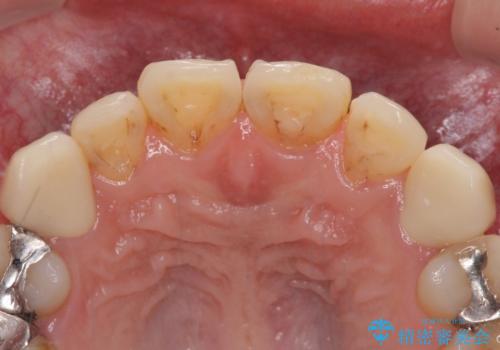

- 以前矯正を行った際に前歯が虫歯だらけとなり、審美面を気にして来院された患者様です。

虫歯の大きかった左右犬歯はオールセラミッククラウンで補綴治療をおこない、4前歯は研磨や古い充填物の詰め直しを行いました。

歯並びは良くなったものの、着色が気になって口元を見せることを躊躇していた用ですが、治療後は他人の視線を気にすることがなくなったようで、大変満足していただきました。